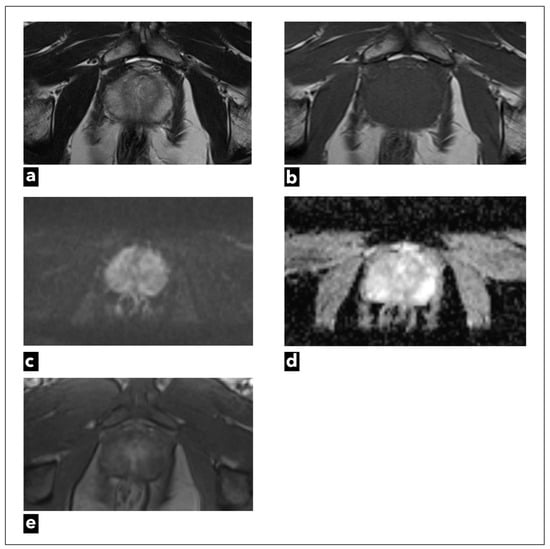

The semi-quantitative method was used in PI-RADS v.1 [8], while the qualitative method of DCE analysis is used in currently valid PI-RADS v.2.1 [9,10]. In the PI-RADS categorisation DCE-MRI has a clear application only in peripheral zone lesions characterised on DWI as PI-RADS 3. If there is an early arterial contrast accumulation in the observed change, it is upgraded to the PI-RADS 4 category, and if there is no early contrast enhancement, the PI-RADS 3 category remains (Figure 4) [9,10].

According to PI-RADS v.2, DCE sequence has no role regarding focal changes in the transition zone, but it is still recommended to record the DCE findings in the transition zone [9,10]. Although the PI-RADS scoring system is widely accepted, there is also an alternative Likert score [85]. The Likert scale has been recommended by National Institute for Health and Care Excellence (NICE) guidelines in the United Kingdom [86]. On the Likert scale, clinical parameters, genetics, and PSA density are taken into account. All sequences are considered equally important, so there is no dominant sequence [87]. Unlike the PI-RADS score, where DCE-MRI is used only as a secondary sequence in peripheral zone cancer, in the Likert score, DCE can have the role of primary sequence for both transitional and peripheral zone cancer [86,87]. Unlike PI-RADS, where DCE can only upgrade the score, Likert DCE can both upgrade and downgrade the score. Also, DCE-MRI is considered positive in PI-RADS only if there is a focal enhancement in a suspicious lesion, while in Likert diffuse early enhancement can also be considered a positive DCE-MRI finding [87,88]. Therefore, DCE-MRI has a more significant role in the Likert score than in PI-RADS.